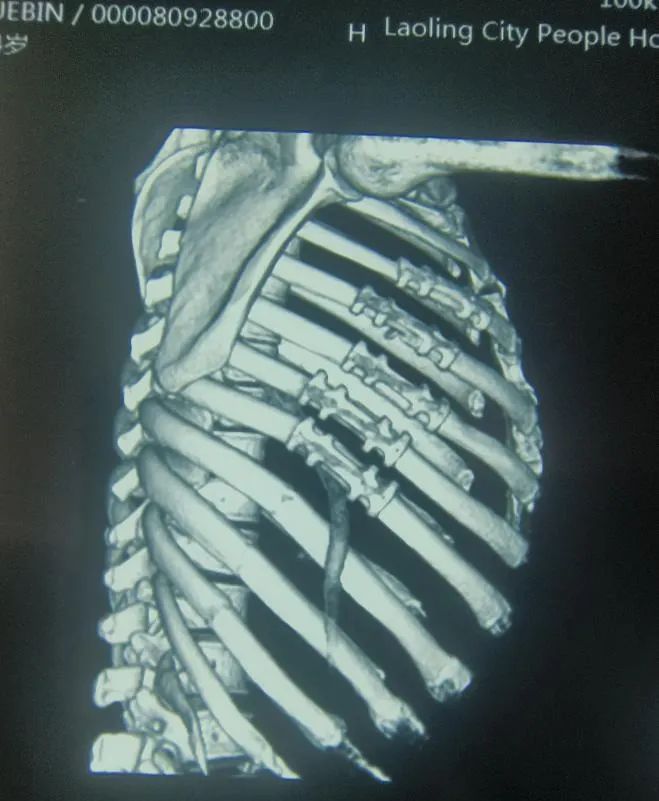

6月17日上午,我院胸外科紧急收治了一位多发肋骨骨折患者。患者中年男性,于工地高处坠落,右侧3-12肋骨骨折、肺部损伤,伤情严重,虽然患者的血氧饱和度暂时稳定,但这伤情像一颗定时炸弹时刻影响着患者的生命健康。经过充分评估,我院胸外科在麻醉科、手术室的通力配合下,及时为患者顺利完成“胸腔镜探查肋骨骨折切开复位内固定术”,患者术后第二天即胸痛缓解、咳嗽有力、能自主正常下床活动。

术前

术后